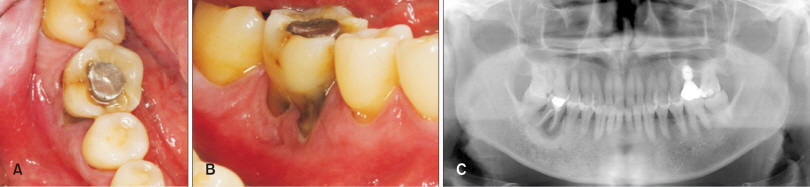

57세 남자 환자가 #46번 치아의 심한 치주염을 주소로 내원하였다. 방사선 사진에서 근단 부위를 넘어선 심한 골파괴와 함께 치조골의 골경화 양상을 관찰할 수 있었다(Fig. 1). 발치 후 자연 치유된다면 추후 치료가 어려워질 것을 예상하여 치조제 보존술을 계획하였다. 염증 조직의 확실한 제거를 위해 판막을 거상하였으며, 발치 후 협측과 근단측으로 연장된 염증성 육아 조직을 철저히 소파하였다. Tetracycline 용액을 cotton ball을 이용하여 발치와벽과 연조직 부위에 적용하였다. 10% 콜라겐이 함유된 탈단백 우골(Bio-Oss®Collagen 250 mg; Geistlich Pharma, Wolhusen, Switzerland)을 과도한 힘을 주지 않으면서 발치와에 적용하였으며 흡수성 콜라겐 차단막(Bio-Gide®; Geistlich Pharma)을 두 겹으로 하여 이식된 탈단백 우골이 완전히 덮이도록 하였다. 판막이 최대한 접합되도록 봉합하였지만, 일차 봉합을 시도하지는 않았다(Fig. 2).

Fig. 1. Clinical and radiologic findings at an initial visit of the patient 1. Clinical photograph at an occlusal view (A), clinical photograph at a facial view (B), panoramic view (C).